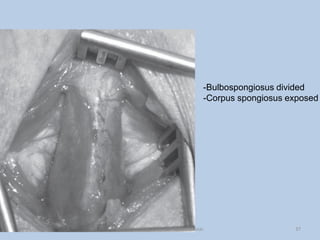

-Bulbospongiosus divided

-Corpus spongiosus exposed

-Bulbospongiosus divided -Corpus spongiosusexposed 37 Dept of Urology, GRH and KMC, Chennai.